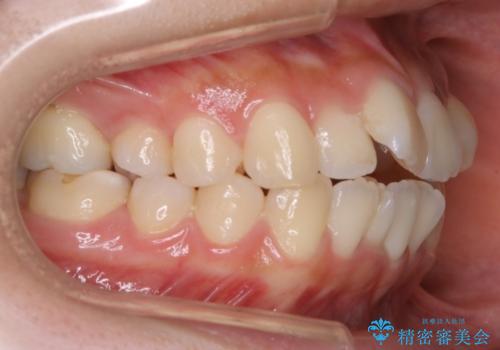

矯正装置の希望がインビザラインだったため、マイクロインプラントを併用し、奥歯から順に遠心移動をかけていくことにより非抜歯でも主訴のガタつきを治すことができました。

マウスピースとマイクロインプラントを組み合わせることで、抜歯をしなくても歯並びを治すためのスペースを作ることができます。奥歯から順に移動させていくので前歯に変化が出るまでには時間がかかりますが、その分健康な歯を抜歯することなく理想的な歯並びを手に入れることができます。